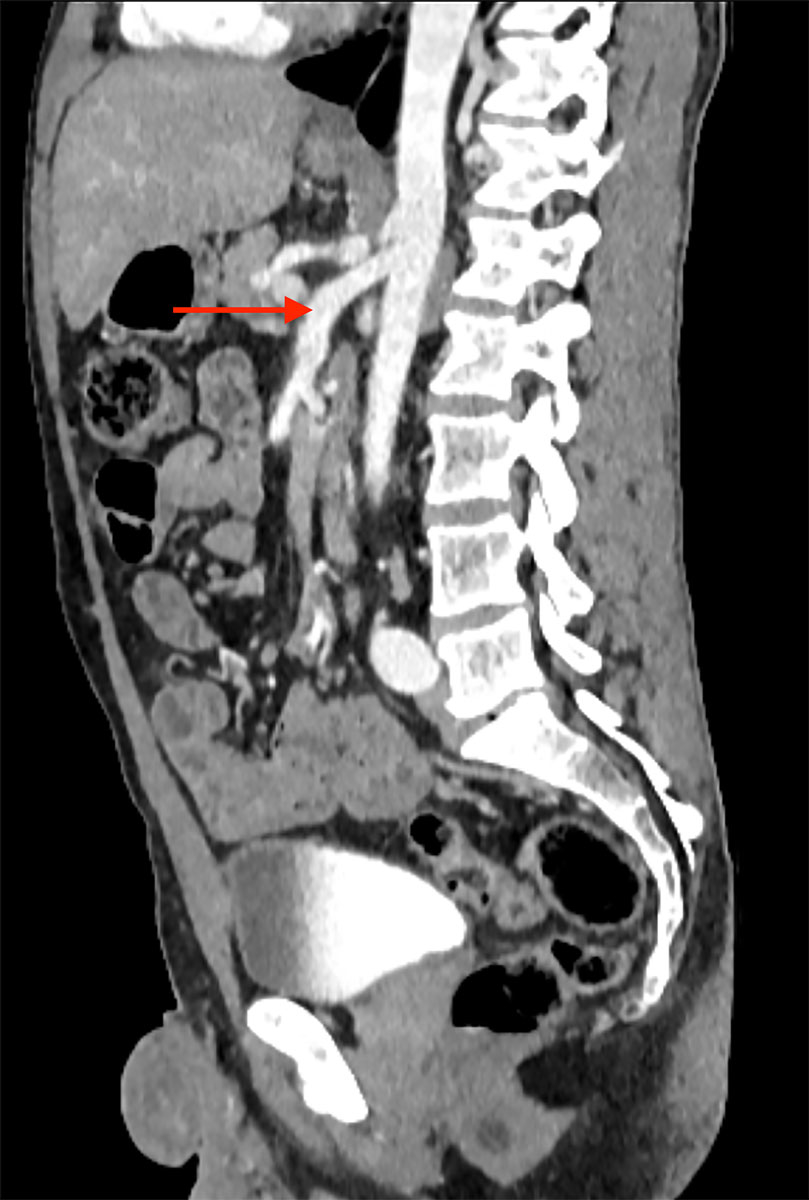

Currently, the patient is recovering well from the latest surgery and is gaining weight. An abdominal CT angiography was recently performed and showed a good blood flow after the superior mesenteric artery angioplasty (fig. 7). Celiprolol treatment is well tolerated and blood pressure is strictly monitored by self-measurements and regularly managed by his general practitioner. Finally, a dedicated rare disease team in our hospital follows the patient closely.

Figure 7 Follow-up abdominal CT scan after balloon angioplasty showing an excellent result.